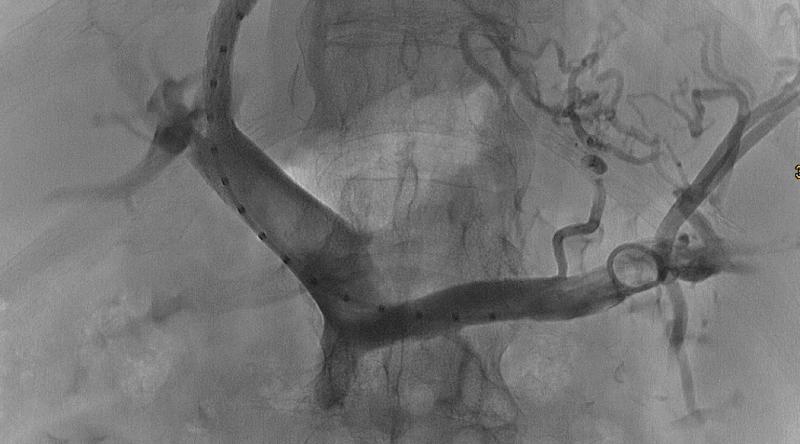

Der TIPS ist eine Intervention zur Behandlung der Komplikationen einer schweren portalen Hypertension. Durch die Verbindung zwischen Lebervene und Pfortader mittels eines Stents wird der hohe Druck in den splanchnischen Gefäßen adäquat gesenkt. Indikationen für einen TIPS sind u.a. Varizenblutung, therapierefraktärer Aszites, hepatorenales Syndrom, Budd-Chiari-Syndrom und splanchnische Venenthrombosen. Eine gute und sorgfältige Auswahl der Patienten, korrekte Durchführung und regelmäßige Kontrolluntersuchungen sind daher notwendig. Die TIPS-Anlage erfolgt interdisziplinär bei unseren Kollegen der Klinik für Diagnostische und Interventionelle Radiologie. Wir betreuen diese Patienten in unserer Spezialambulanz TIPS.

Pfortaderrekanalisation

In seltenen Fällen kann es zu einer akuten nicht-zirrhotischen Thrombose von Pfortader und anderen splanchnischen Thrombosen kommen. Diese Situation ist äußerst bedrohlich und sollte umgehend an einem Zentrum behandelt werden. Das CCB hat als eines von wenigen Zentren in Deutschland die Möglichkeit solche Thrombosen interventionell mit Thrombaspiration und lokaler Thrombolyse zu behandeln.

Auch chronische Thrombosen der splanchnischen Gefäße können bei ausgewählten Patienten am CCB rekanalisiert werden.

Für diese Interventionen arbeiten wir eng mit den Kollegen der Klinik für Diagnostische und Interventionelle Radiologie zusammen.